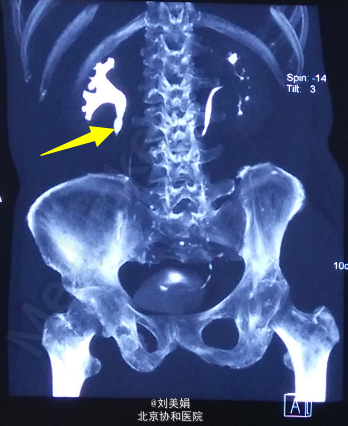

主 诉:体检发现右肾结石8个月 现病史:患者2014-11体检超声发现右肾结石,未予特殊诊治。2015-03因“类风湿性关节炎”入住我院普通内科,期间查泌尿系超声:右侧输尿管上段宽0.7cm,内见条状强回声,长约1.8cm,后伴声影,右侧输尿管中下段显示欠清。考虑右输尿管上段结石伴输尿管稍扩张,右肾盂分离。行CTU检查:右肾盂-输尿管连接处(UPJ)见类圆形密度增高影,大小约15mm×10mm,平扫CT值约1255Hu,其近端输尿管及右肾盂肾盏轻度扩张积水,壁略增厚毛糙,病灶周围见多发索条影。 小便夜尿增多,3-5次/晚,一年体重下降3kg。 右肾区轻度叩击痛,右输尿管走行区轻度压痛。

泌尿系结石双能量CT+成分分析:右输尿管-肾盂连接处(UPJ)见类圆形高密度影,大小约13mm×10mm,CT值约1049Hu,其近端输尿管及右肾盂肾盏扩张积水,输尿管及肾盂壁略增厚毛糙,病变周围多发索条影。左侧肾盂肾盏及输尿管未见明显异常。前列腺增大伴钙化灶。 泌尿系结石双能量成分分析:右UPJ结石主要成分为草酸盐。

右输尿管结石 右侧输尿管镜下碎石术

该患者,结石导致肾盂扩张,必须择期行输尿管镜下碎石或PCNL,积极治疗,保护右肾功能。 输尿管镜手术要是有狭窄环,可留置D-J管,拟二期处理结石。